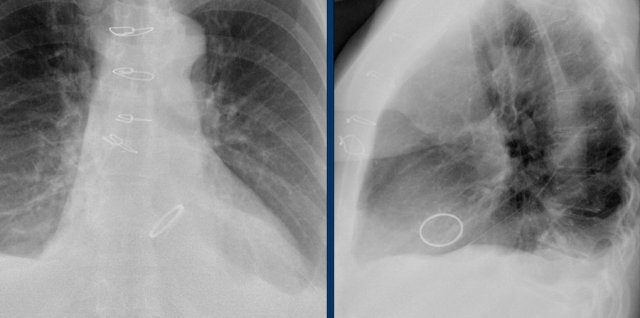

The images show a pacemaker with an atrial and ventricular lead.

The tip of the atrial lead is pointed upward and anteriorly, because the ideal position is in the right atrial appendage, where it is anchored within the coarse trabeculae.

The tip of the ventricular lead is positioned in the apex of the right ventricle, which is located to the left of the spine on a frontal chest X-ray and anteriorly on a lateral view.

Here an example of an ICD with wires in the right atrial appendage, the apex of the right ventricle and a lead to the left ventricle in the posterior coronary vein.

You can recognize the two shock coils of the ICD as thicker white bands along the course of the lead.